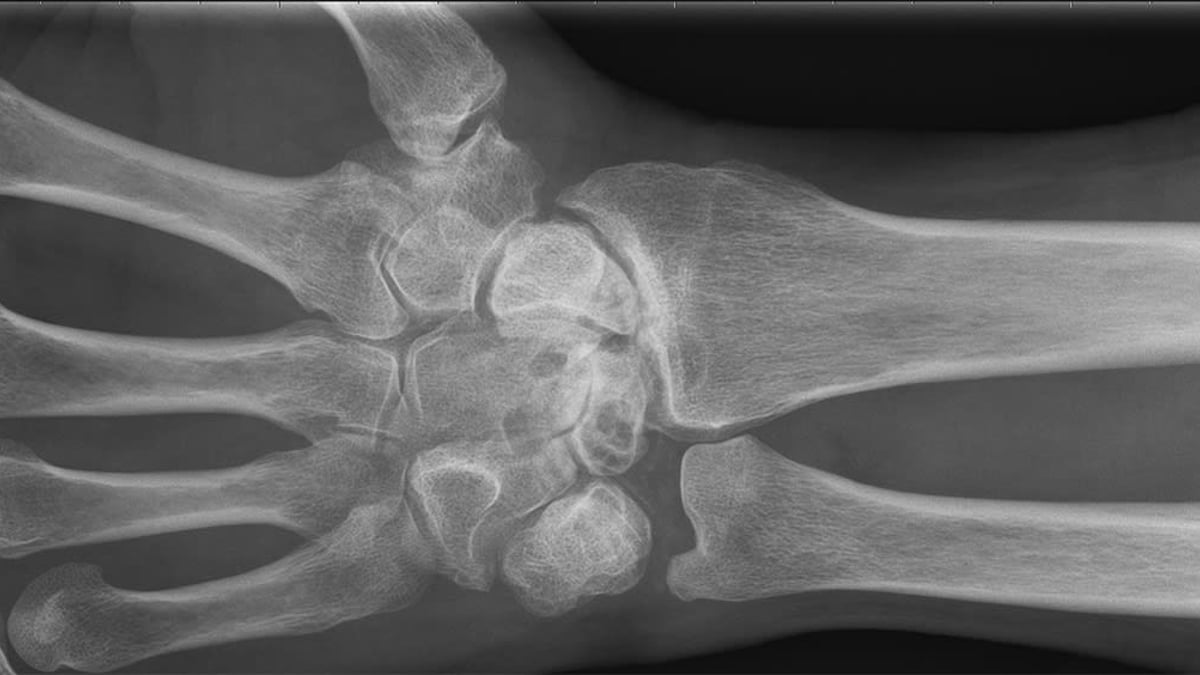

Röntgenbilden visar en handled som är totalförstörd på grund av avsaknad av brosk. Tack vare operationsmetoden handledsdenervation slapp patienten stelopereras och är idag smärtfri.